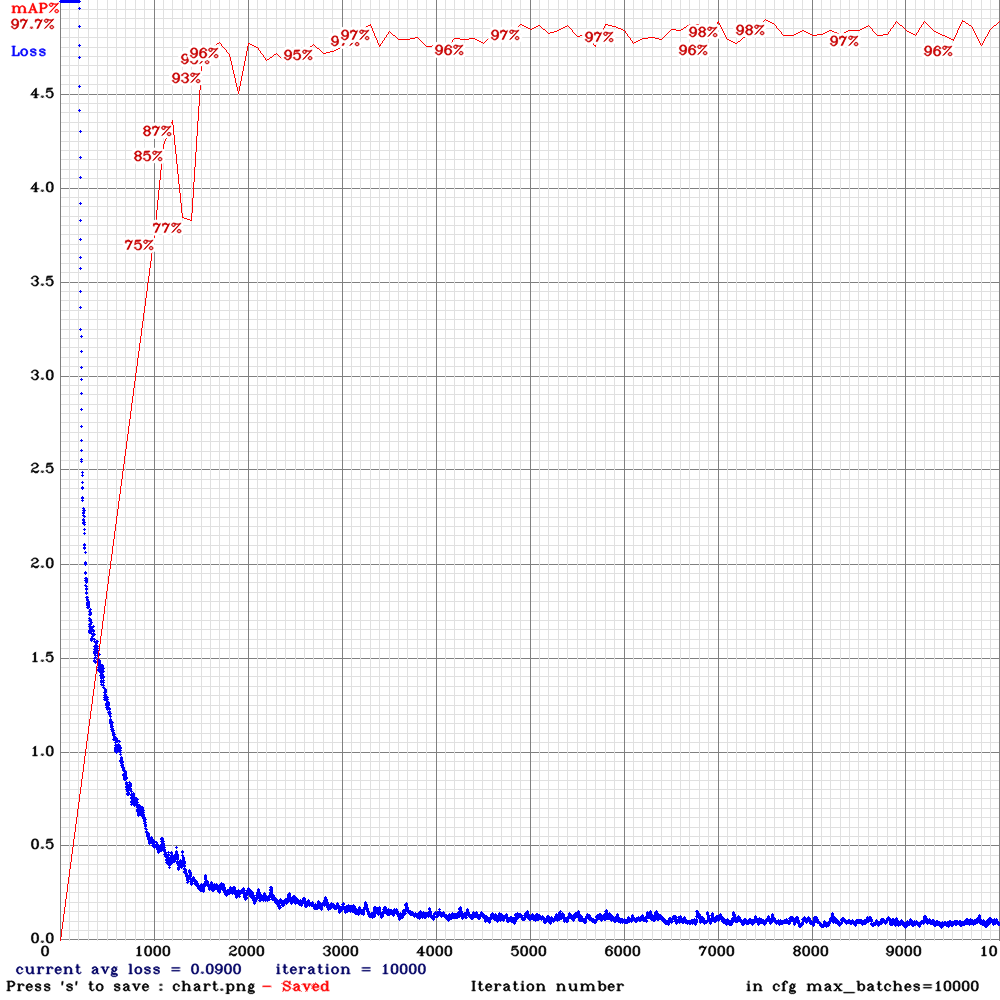

This section reports the polyp detection performance of the proposed CNN model. For implementation of the model, 80.00% and 20.00% of the 2,156 augmented polyp frames were used for training and testing, respectively. Fig. 5 shows the real-time training phase of the proposed model, where 10,000 iterations were run to achieve the best weights. The model was trained using the simulation parameters as given in Table. 1, both for the non-augmented ETIS-Larib database [34] containing 196 poly images, and the augmented data set, for fair performance comparison. A high mean average precision of 97.70% with an MSE of 0.900 was obtained in the early iterations, resulting in the best weights for testing purposes.